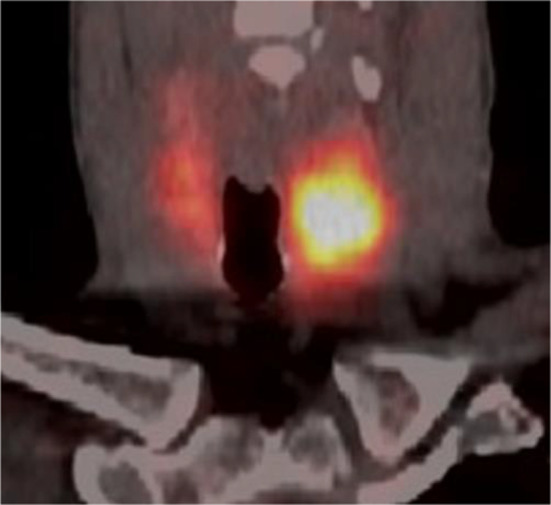

Fig. 2.

68Ga-DOTATATE PET/CT coronal fusion image showing high uptake in the left thyroid nodule and mild and diffuse physiological uptake in the right lobe

A 51-year-old male presented with significant weight loss and fatigue for several months with a history of hypertension and gastroesophageal reflux disease. Clinical examination revealed a left palpable thyroid nodule. All routine blood tests, including a complete hemogram, renal function and liver function, were normal. Thyroid function tests were within the normal range as were serum levels of parathormone (PTH), Chromogranin A (CgA), carcinoembryonic antigen (CEA) and calcitonin. Ultrasonographic neck imaging showed bilateral intermediate-risk EU-TIRADS 4 thyroid nodules. The largest nodule, measuring 23 × 26 × 35 mm, was located in the left lobe. Thyroid scintigraphy using technetium-99 m pertechnetate showed a cold nodule located in the left lobe (Fig. 1). Fine-needle aspiration biopsy (FNAB) of the nodule did not demonstrate cellular atypia (Bethesda category II). For unknown reasons, 111In-DTPA-octreotide scintigraphy was requested by the treating physician and displayed a high focal uptake in the left nodule. The same findings were observed on the 68Ga-DOTATATE PET/CT, with a SUVmax of 13.8 (Fig. 2). No other sites of pathological uptake were detected. The patient was discussed at the multidisciplinary tumor board meeting. Given the presence of bilateral thyroid nodular lesions, the decision was to perform a near-total thyroidectomy associated with a prophylactic neck dissection of level VI. Histopathological findings revealed a multinodular goiter containing a microfollicular adenoma without malignancy. Immunohistochemical analysis of calcitonin, CgA, synaptophysin and somatostatin receptor subtype 2 (SSTR2) expression was performed. Results did not suggest neuroendocrine neoplasia or C cell hyperplasia. Higher expression of SSTR2 was observed in the microfollicular adenoma compared to the surrounding healthy tissue, with predominant localization in the endothelial cells and at the secretory pole of the thyroid epithelial cells in contact with blood vessels (Figs. 3, 4).

In the present case, the incidental finding of a high focal thyroid uptake with a SUVmax of 13.8 as detected by 68Ga-DOTATATE PET/CT raised suspicion for thyroid malignancy. Histopathological and immunohistochemical analyses revealed a benign adenomatous nodule with overexpression of SSTR2. Remarkably, the high density of SSTR2 was predominantly localized in endothelial cells. High endothelial expression of SSTR has been reported in both malignant and benign lesions such as lymphoma, hemangioma and thymoma (Ruuska et al. 2018; Brogsitter et al. 2014; Ferone et al. 2001). The presence of SSTR on endothelial cells is thought to contribute to tissue growth, however, precise clinical significance remains unclear (Watson et al. 2001).